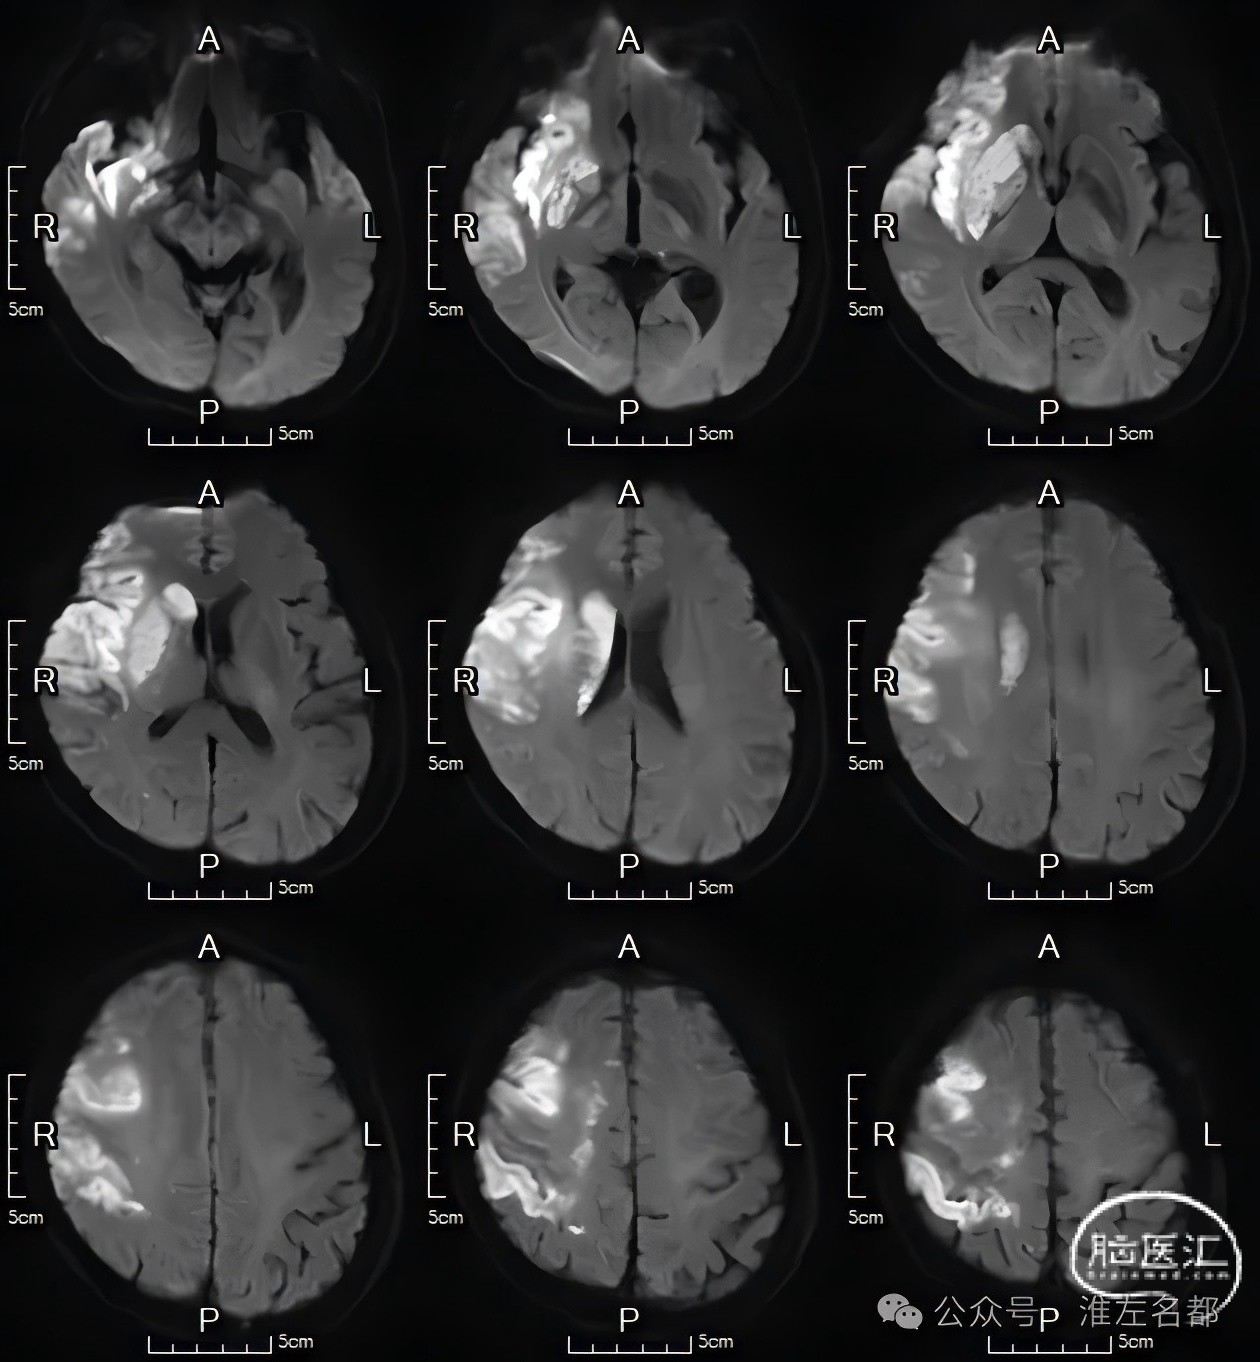

术后第4天MRI

DWI:右侧基底节和额颞叶大范围高信号。

颅脑3D-TOF-MRA:右侧大脑中动脉和双侧大脑前动脉显影通畅。